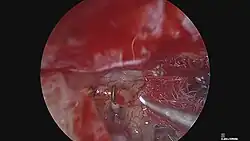

Stapedectomy

Stapedectomy is a surgical procedure in which the stapes bone is removed from the middle ear and replaced with a prosthesis.

Stapedotomy

A modified stapes operation, called a stapedotomy, is thought by many otologic surgeons to be safer and reduce the chances of postoperative complications. In stapedotomy, instead of removing the whole stapes footplate, a tiny hole is made in the footplate – either with a microdrill or with a laser,[7] and a prosthesis is placed to touch this area, oval window. This procedure can be further improved by the use of a tissue graft seal of the fenestra, which is now common practice.[5]

Laser stapedotomy is a well-established surgical technique for treating conductive hearing loss due to otosclerosis. The procedure creates a tiny opening in the stapes (the smallest bone in the human body) in which to secure a prosthetic. The CO2 laser allows the surgeon to create very small, precisely placed holes without increasing the temperature of the inner ear fluid by more than one degree, whilst decreasing the risk of footplate fracture, making this an extremely safe surgical solution.[8] The hole diameter can be predetermined according to the prosthesis diameter. Treatment can be completed in a single operation visit using anesthesia, normally followed by one or two nights' hospitalization with subsequent at-home recovery time a matter of days or weeks.

Endoscopic Stapedotomy

In 1999, Professor Tarabichi described his experience with stapedotomy performed using the endoscope without the need for bone removal or skin incision (endaural approach).[9] Since then, endoscopic stapedotomy has been gaining popularity especially amongst younger endoscopically trained surgerons. It allows for better view of the footplate of the stapes without the need to remove bone which is very common when doing the procedure with microscope.[17] Professor Patel and his Australian team published a relatively large cohort of patients undergoing endoscopic stapedotomy procedure with closure of air-bone gape within 20 dB in 98.6%.[18]